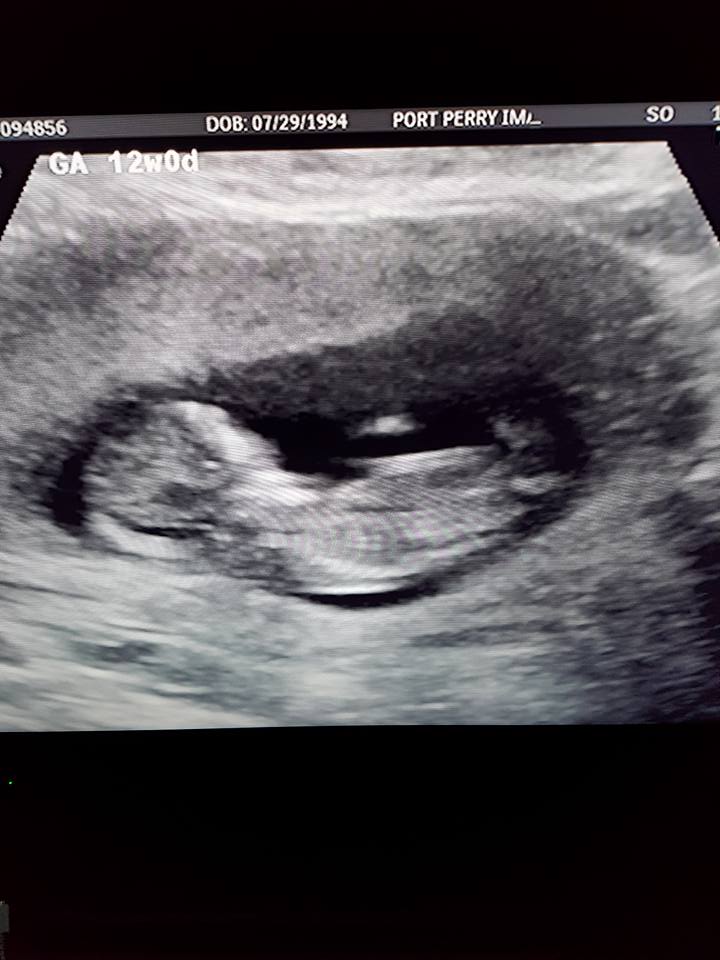

Hi! Just wondering if there is a nub in these photos, and if so, if you would guess it's a boy or girl? 12+0 weeks. Thank you!Attachment 38349Attachment 38350Attachment 38351Attachment 38352Attachment 38353